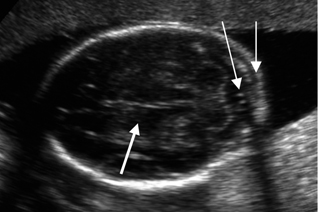

Εικόνα 2. Διαθαλαμική απεικόνιση κρανίου. Μέτρηση BPD (γραμμή), δρέπανο (μακρύ βέλος), οπτικοί θάλαμοι (λεπτό βέλος) και διαφανές διάφραγμα (κοντό βέλος). Εικόνα 3. Διαπαρεγκεφαλιδική απεικόνιση. Εμφανής η παρεγκεφαλίδα, η μεγάλη δεξαμενή (μακρύ βέλος), οι οπτικοί θάλαμοι (παχύ βέλος) και η αυχενική πτυχή (κοντό βέλος). Εικόνα 4. Διακοιλιακή απεικόνιση με μέτρηση της διαμέτρου της πλάγιας κοιλίας. Παρουσία χοριοειδούς πλέγματος εντός (βέλος).

Εικόνα 17. Διακοιλιακή τομή κρανίου με σχήμα lemon sign, λόγω παραμόρφωσης μετωπιαίων οστών. Εικόνα 18. Διαπαραγκεφαλιδική απεικόνιση κρανίου με banana sign παρεγκεφαλίδα (βέλος). Εικόνα 19. Υπερδιάταση πλαγίων κοιλιών, ατροφία του εγκεφαλικού παρεγχύματος λόγω πίεσης (βέλος).